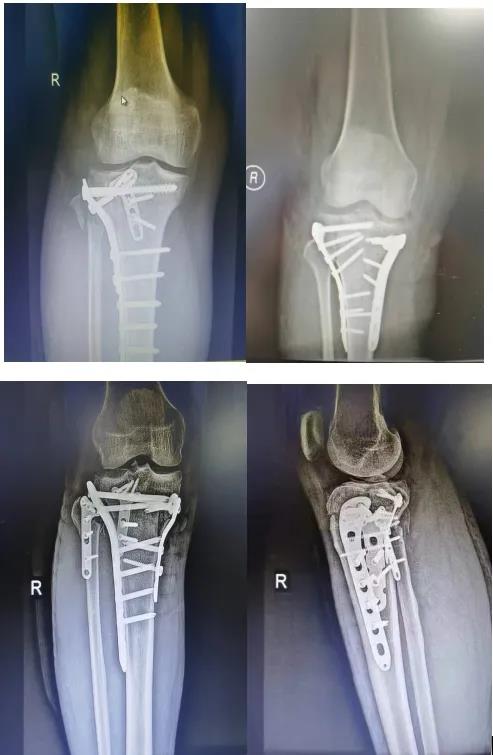

膝关节外科技术力量雄厚,科室配备医护人员30人,其中,主任医师5名,副主任医师3名,主治医师3名,住院医师4名,博士1名,硕士研究生4名。开放床位48张。该科擅长对膝关节严重创伤(包括股骨远端骨折、髌骨骨折、胫骨平台骨折等)、膝骨关节炎阶梯化治疗、保膝治疗、膝关节微创单髁置换术、全膝关节置换术、膝关节翻修术具有丰富的临床诊疗经验,追求微创、无痛、快速康复。对膝关节骨性关节炎采取阶梯化治疗方案,坚持中西并重、内外兼治的原则,取得满意的治疗效果。早期利用中医中药的传统优势,使用中医外治法,例如烫熨治疗、中药涂擦、雷火灸、中药塌渍等,同时辩证内服本院中药制剂及内服方药以及配合西药治疗,开展健康教育,运用运动疗法、物理治疗等辅助支持;中期开展软骨修复、截骨术、单髁置换术、髌股关节置换术等;对于终末期的膝关节OA采用全膝关节置换术。【膝关节外科主要特长】 (一)膝骨关节炎高位截骨术

(五)胫骨平台骨折内固定术

(六)膝关节置换术后假体周围骨折内固定术